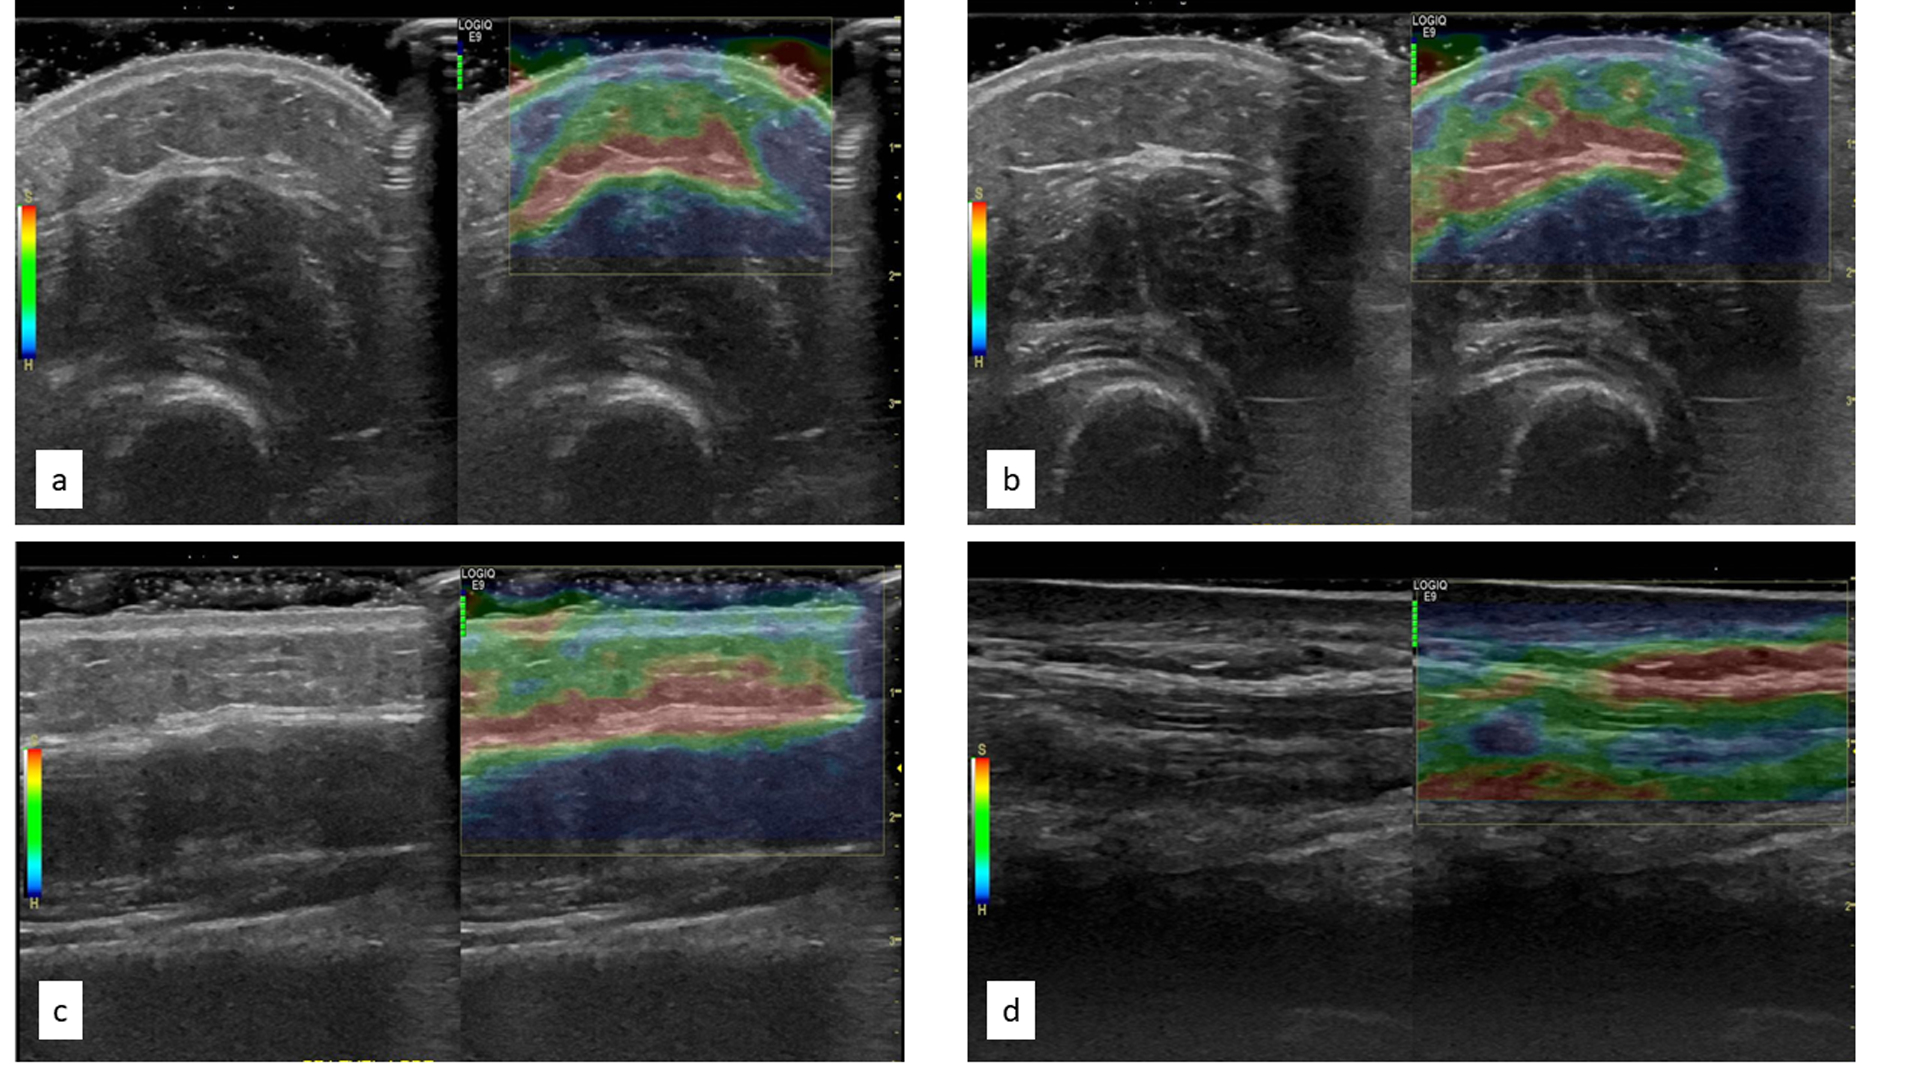

No significant or interpretable signals were identified in any of the color Doppler images and consequently, no further analysis was completed. Analysis of strain elastography in short-axis images was difficult as the rounded shape of the forearm led to artifacts. These artifacts were realized as different shades of blue and green within the dermal layer clearly affected differentially by underlying bone as demonstrated in Figure 3a and 3b. Similar inconsistencies in color were noted in strain elastography images obtained with the transducer floating (Figure 3c), likely due to uneven wave compression resulting from not pushing on the skin surface. Strain imaging in long-axis with the transducer placed on the surface was the only valid technique without artifacts (Figure 3d). However, upon review, these strain images were considered to have low reliability as significant shifts in coloration were noted among repeated images obtained at the same location during the same time point (i.e., pre- or post-treatment). No further analysis of strain elastography images were conducted.

Figure 3.

Pre-post treatment elastography images in short axis (a, b) and elastography image longitudinal floating versus surface (c, d respectively)